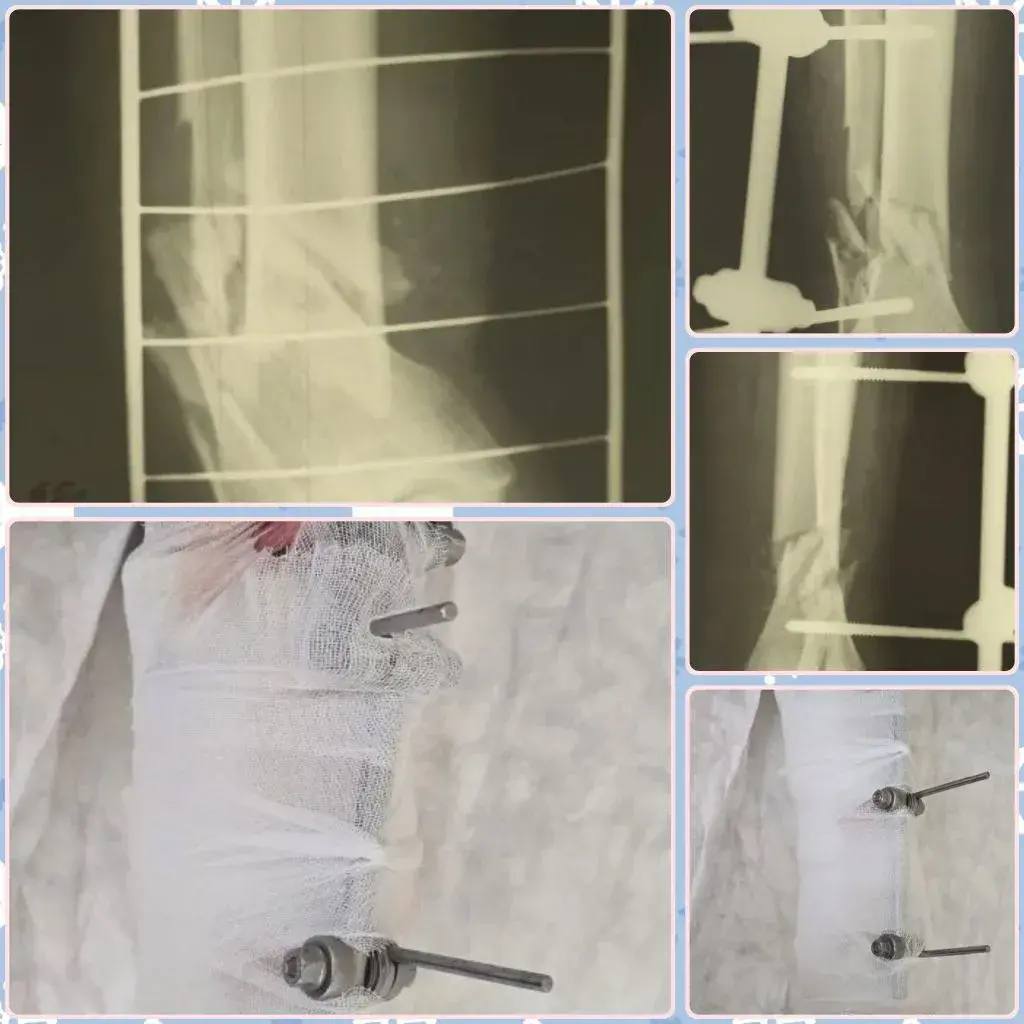

Следующий случай произошел из-за мытья окон. 65-летний мужчина, стоя на стремянке, не удержал равновесие и упал. Диагноз - тяжелый открытый многооскольчатый перелом обеих костей голени со смещением и обширной раной. Врачи стабилизировали перелом с помощью специального аппарата, но впереди у пациента - месяцы реабилитации.